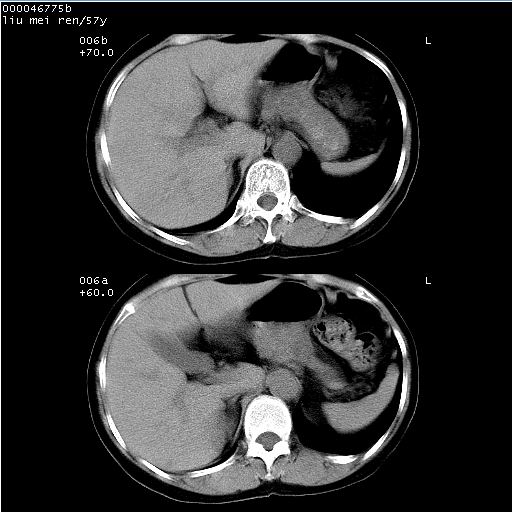

患者 女,57岁。因车祸受伤,其家属要求行“全身ct检查”。平素健康。

胸部ct轴位平扫(层厚10mm,螺距1.5,重建间隔10mm),图像如下: